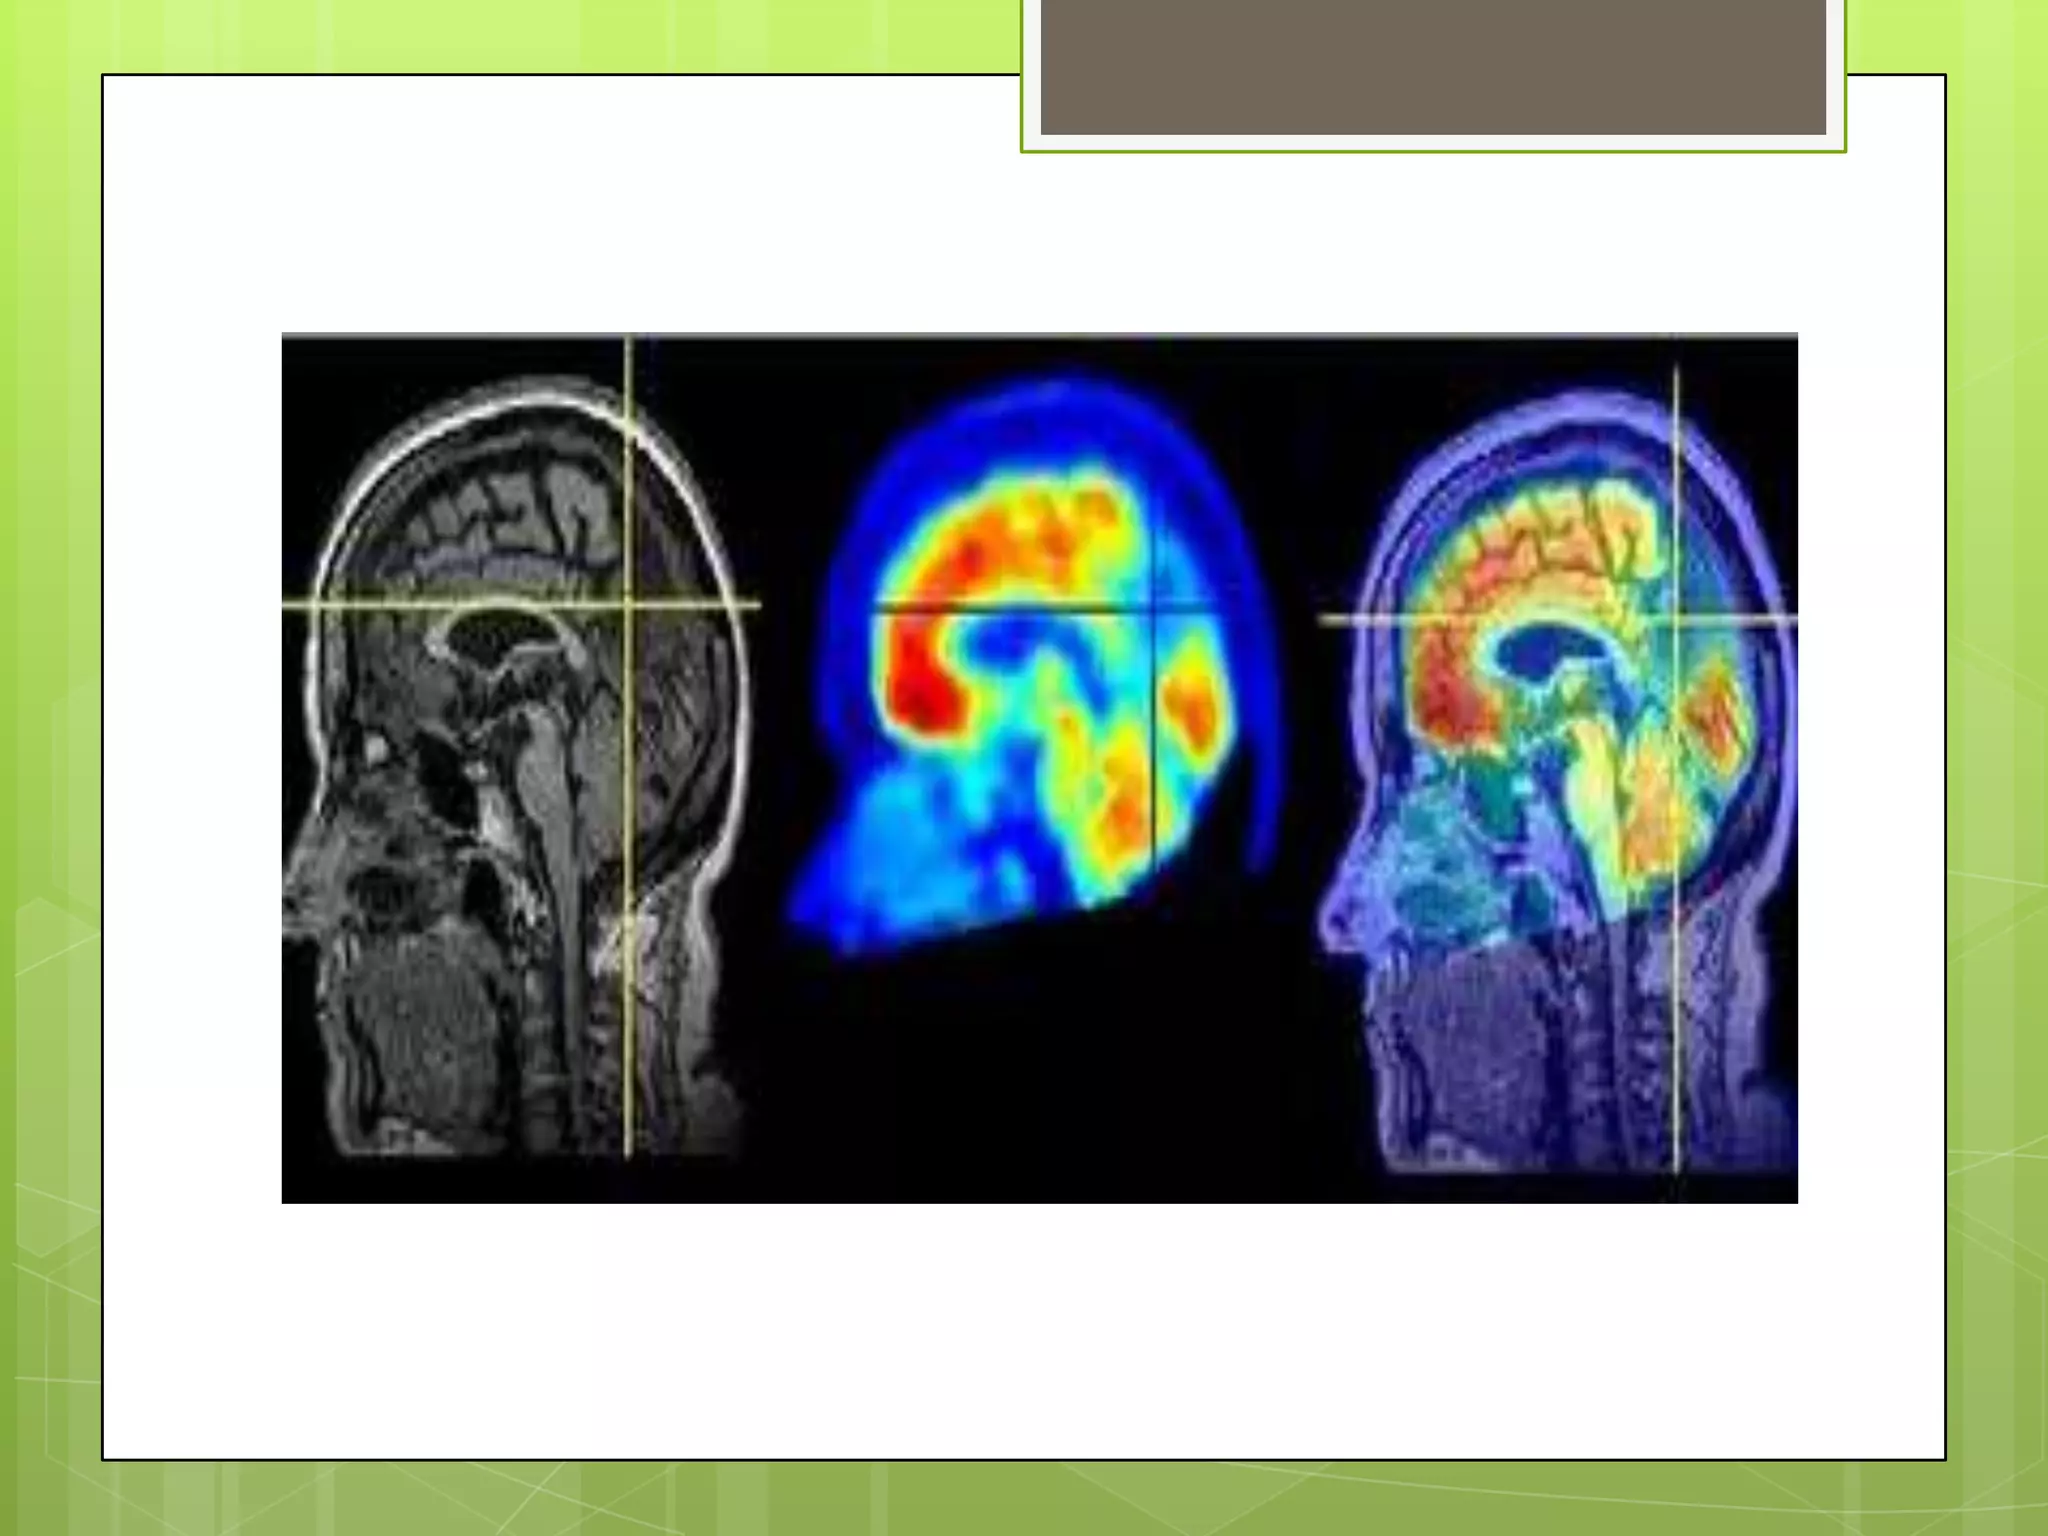

Las Imágenes por Resonancia

magnética

 Usan radioondas generadas por computadora y un

campo magnético poderoso para producir imágenes

detalladas de estructuras del cuerpo como tejidos,

órganos, huesos y nervios.

 Los usos neurológicos comprenden el diagnóstico de

tumores cerebrales y de la médula espinal,

enfermedades oculares, inflamación, infección, e

irregularidades vasculares que pueden llevar al

accidente cerebrovascular.

 Las IRM también pueden detectar y monitorizar

trastornos degenerativos como la esclerosis múltiple

y puede documentar lesiones cerebrales debidas a

trauma.

LA TOMOGRAFIA CON

EMISION DE POSITRONES

 Proporciona imagines bi y tridimensionales de la

actividad cerebral midiendo los isótopos

radioactivos que se inyectan dentro del torrente

sanguíneo.

 Las tomografías PET cerebrales se usan para

detectar o resaltar tumores y tejidos enfermos, medir

el metabolismo celular y tisular, mostrar el flujo

sanguíneo, evaluar a los pacientes con trastornos

convulsivos que no responden a la terapia médica y

pacientes con ciertos trastornos de la memoria, y

determinar cambios cerebrales luego de lesiones o

abuso de drogas, entre otros.

Las Imágenes porResonancia magnética  Usan radioondas generadas por computadora y un campo magnético poderoso para producir imágenes detalladas de estructuras del cuerpo como tejidos, órganos, huesos y nervios.  Los usos neurológicos comprenden el diagnóstico de tumores cerebrales y de la médula espinal, enfermedades oculares, inflamación, infección, e irregularidades vasculares que pueden llevar al accidente cerebrovascular.  Las IRM también pueden detectar y monitorizar trastornos degenerativos como la esclerosis múltiple y puede documentar lesiones cerebrales debidas a trauma.

LA TOMOGRAFIA CON EMISIONDE POSITRONES  Proporciona imagines bi y tridimensionales de la actividad cerebral midiendo los isótopos radioactivos que se inyectan dentro del torrente sanguíneo.  Las tomografías PET cerebrales se usan para detectar o resaltar tumores y tejidos enfermos, medir el metabolismo celular y tisular, mostrar el flujo sanguíneo, evaluar a los pacientes con trastornos convulsivos que no responden a la terapia médica y pacientes con ciertos trastornos de la memoria, y determinar cambios cerebrales luego de lesiones o abuso de drogas, entre otros.